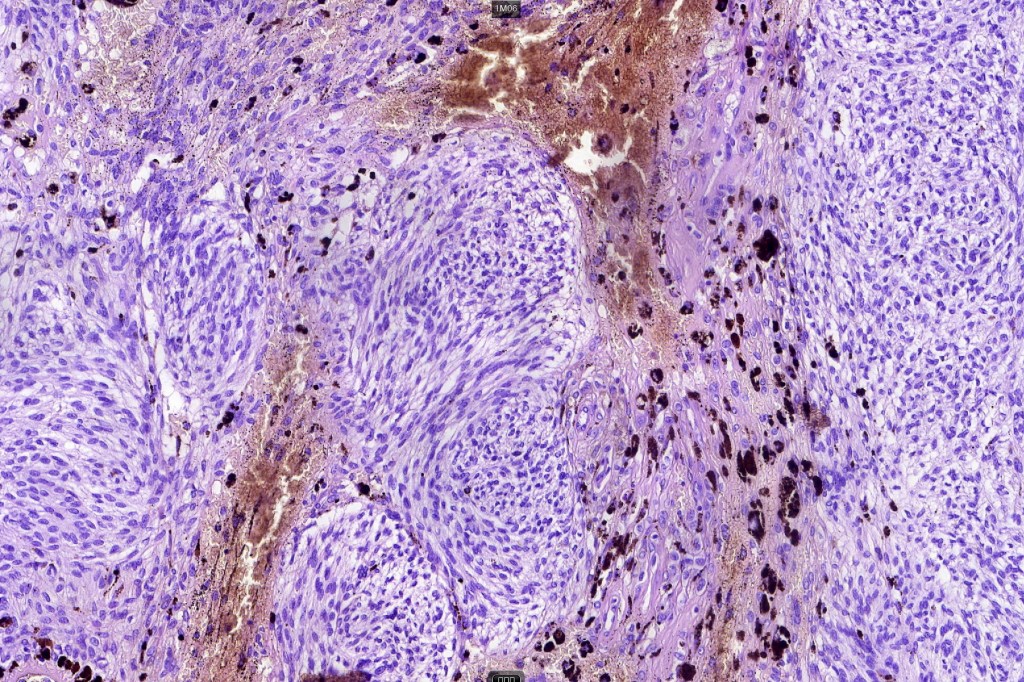

•Admixture of spindle cells, pigmented bipolar or dendritic cells & melanophages

•Cytoplasm is pale and nuclei are small with inconspicuous nucleoli

•An alveolar pattern is characteristic particularly with clear cell nodules

•Multinucleate giant cells sometimes present

•Stromal fibrosis, myxoid change, vascular hyalinization with cyst formation are often seen

•Some tumors are composed spindle cells in a fascicular or neuronevoid pattern

•Perineural involvement may be seen